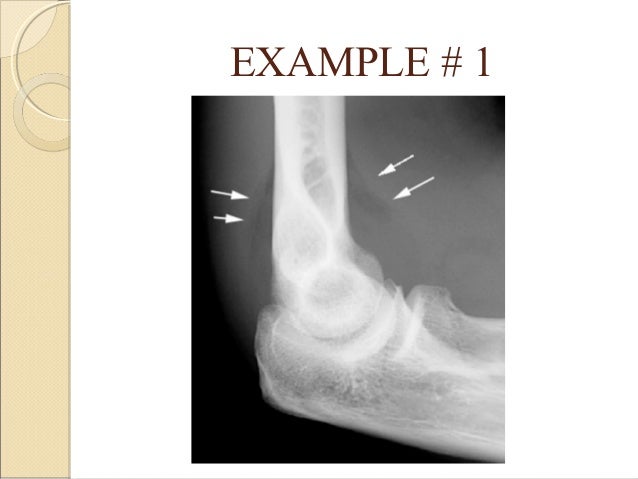

Basics of orthopedic radiology

Christopher gee and alexander young. Mark rodrigues and zeshan qureshi. The entire body's worth of orthopedic fractures!